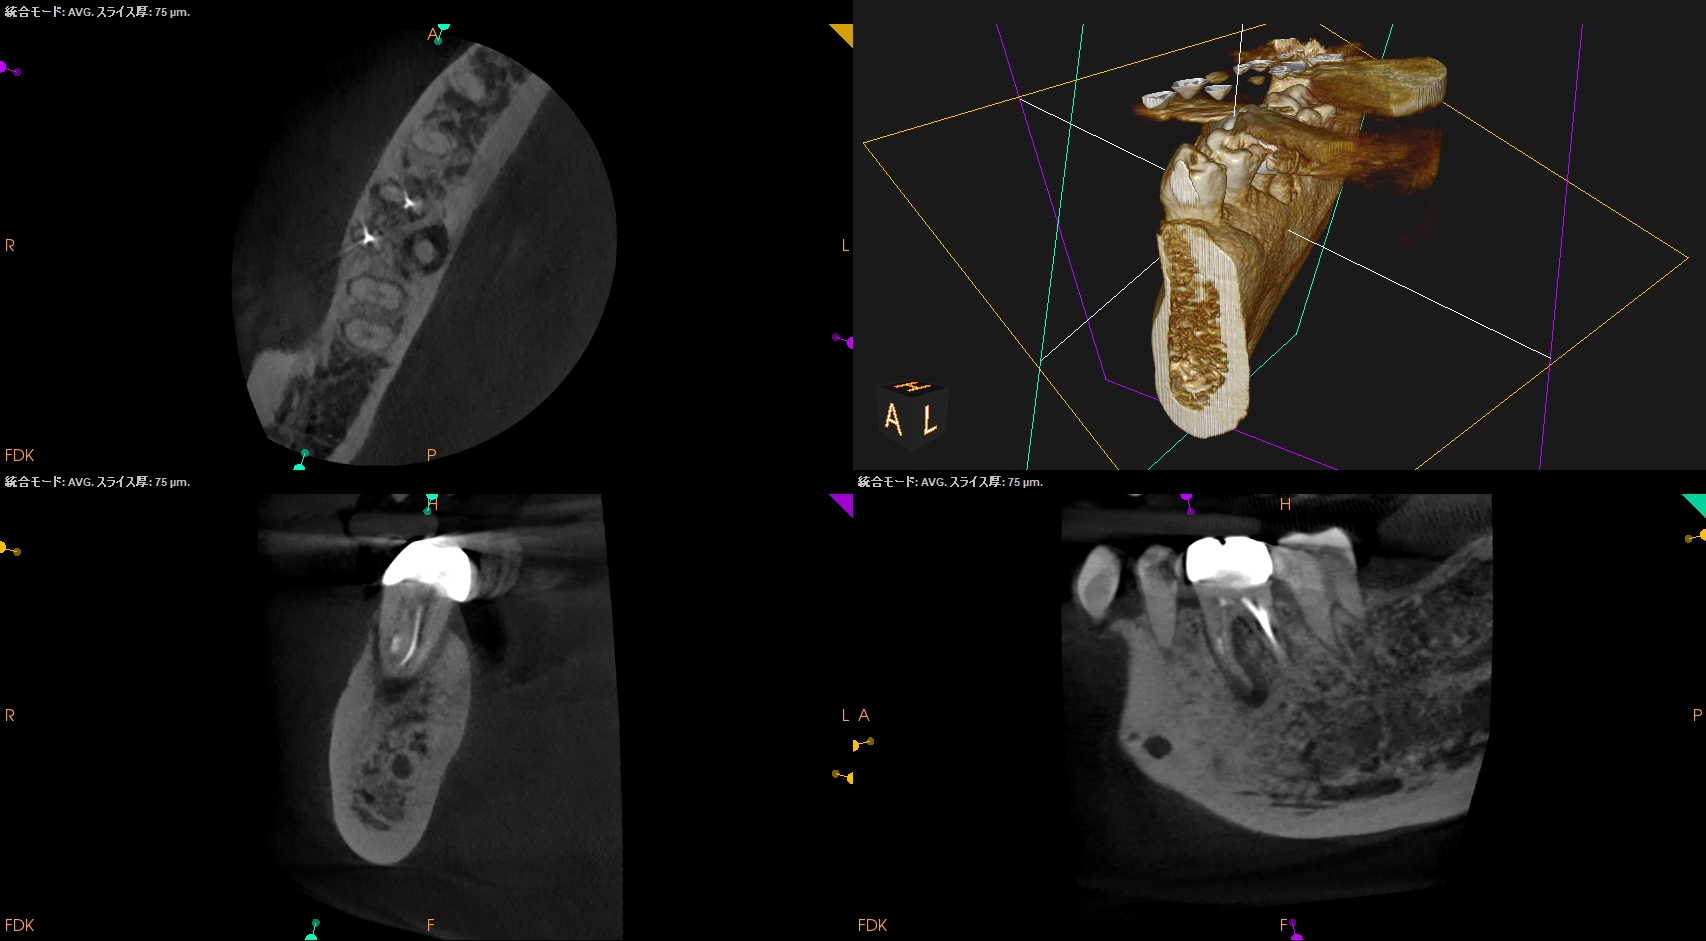

支台築造後にPA, CBCTを撮影した。

MB

ML

D

Radix

問題はないだろう。

ここから時間が1年経過した。

#30 Re-RCT 1yr recall(2026.3.10)

初診時と比較した。

病変は完治した。

このことから最終補綴もOKだし、経過観察も終診とさせていただいた。